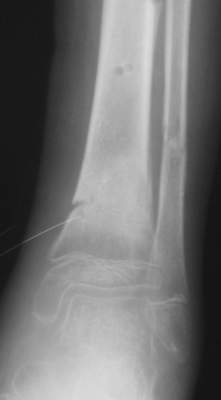

Формирование некроза кожи по задней поверхности н\3 голени~ 1 %, вторичное заживление, кожная пластика. Нейропатия м\берцового нерва (отсутствие активного разгибания 1 пальца) На вытяжении около 8 нед, в дальнейшем в гипсовых повязках ~ 8 мес.

В январе 2005: варусная деформация н\3 голени, болевой с-м, комбинированная контрактура г\стопного сустава, нейропатия м\берцового нерва сохраняется слабость разгибания 1 пальца.

A> В январе 2005: варусная деформация н\3 голени,

А на вытяжении и в гипсповязке в течение 4 мес варуса видно не было?

Чего было ждать?

Деформация появилась и наростала во времени при фиксации в гипсовых повязках.

Были сложности с режимом и лечением( я не зря указал статус ребенка и снижение

Это сросшийся перелом малоберцовой кости. И ложный сустав

н\3 б\берцовой кости.

Промежуточный